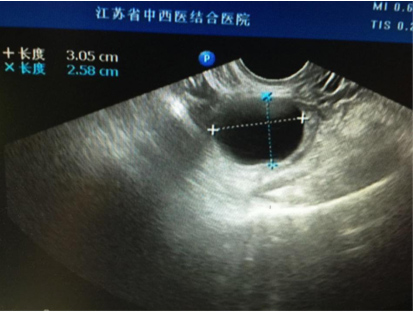

王女士,今年36岁,单位体检发现一侧卵巢有一直径约4cm大小的囊肿,没有什么不舒服,一听说有卵巢囊肿,王女士很紧张的来到我们妇科门诊就诊,问:“医生,我现在该怎么办?我这

个囊肿会不会是癌症?需不需要马上就手术?……”

大部分卵巢囊肿都是卵巢排卵后卵巢修复过程中形成的,多随卵巢周期性变化而产生和消失,因此常见于生育年龄的女性。对于卵巢排卵,多数卵巢外观不会出现明显的变化,只有少数情况形成囊肿,一般形成的囊肿也不会太大,一般是一侧卵巢可见囊肿,我们临床医生称之为“生理性囊肿”,并且多数以5cm为界限,也有以8cm为界限。也就是说5cm之内的“生理性囊肿”,我们不需要采取任何措施,囊肿多数会自然消退,持续的时间长短因个人而异,有持续1个月或数月不等,通常会在三个月内自行消失。而对于超过5cm的囊肿,或持续存在,或变大,可能是病理性囊肿,比如卵巢囊性畸胎瘤、各种囊腺瘤,甚至少数是囊腺癌,因此这种情况下,我们建议手术治疗。